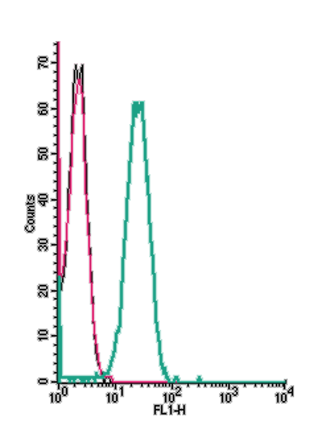

Expression of CXCR5 in human LNCaP cellsCell surface detection of CXCR5 in intact living human prostate carcinoma (LNCaP) cells. A. Extracellular staining of cells using Anti-Human CXCR5 (extracellular) Antibody (#ACR-015), (green), (1:25) merged with live view of the cells (magnitude X40). B. Extracellular staining of LNCaP cells merged with live view of the cells (magnitude X100).

Expression of CXCR5 in human LNCaP cellsCell surface detection of CXCR5 in intact living human prostate carcinoma (LNCaP) cells. A. Extracellular staining of cells using Anti-Human CXCR5 (extracellular) Antibody (#ACR-015), (green), (1:25) merged with live view of the cells (magnitude X40). B. Extracellular staining of LNCaP cells merged with live view of the cells (magnitude X100).

Alomone Labs is pleased to offer a highly specific antibody directed against an epitope of the human CXCR5. Anti-Human CXCR5 (extracellular) Antibody (#ACR-015) can be used in western blot, immunocytochemistry, and indirect flow cytometry applications. The antibody recognizes an extracellular epitope and is thus ideal for detecting the receptor in living cells. It has been designed to recognize CXCR5 from human samples only.